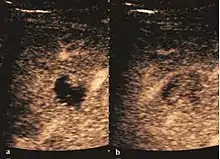

They can be single or multiple, with variable size, generally less than 20 mm (congenital). Rarely, sizes can reach several centimeters, leading up to the substitution of a whole liver lobe (acquired, parasitic). They may be associated with renal cysts; in this case the disease has a hereditary, autosomal dominant transmission (von Hippel Lindau disease).

The ultrasound appearance is a well defined lesion, with very thin, almost unapparent walls, without circulatory signal at Doppler or CEUS investigation. The content is transonic suggesting fluid composition. The presence of membranes, abundant sediment or cysts inside is suggestive for parasitic, hydatid nature. Posterior from the lesion the acoustic enhancement phenomenon is seen, which strengthens the suspicion of fluid mass. They typically displace normal liver vessels but no vascular or biliary invasion occurs.